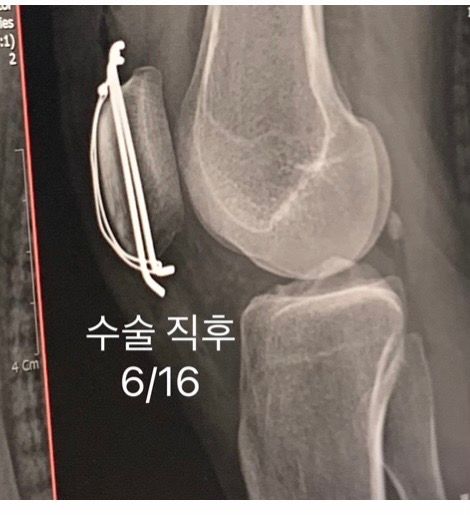

슬개골 골절 후 철심수술 와이어변형 이대로 두어도 괜찮을까요?

6/13일 슬개골 골절로 철심 박는 수술 후 붕대 및 지지대 처리를 하고 입원하였습니다 6/27일 퇴원 예정이라 6/26일 엑스레이를 찍었는데 와이어가 돌아가서 갑자기 통깁스를 하게 되었어요 의사분 말로는 와이어가 돌아가도 재수술이나 향후 재활엔 크게 문제가 없으나 고정이 필요하다고 해 일주일간 통깁스를 하게 된건데 정말 문제가 없는게 맞나요?

• 1번 째 사진